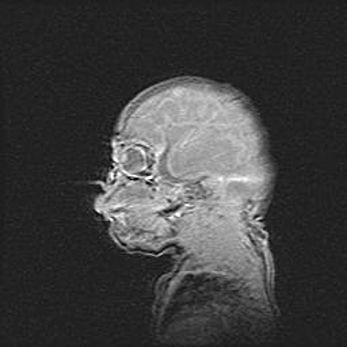

Открытая гидроцефалия.

Возраст: 6 месяцев 15 дней

Вес: 6200 г

Пол: женский

Окружность головы: 41 см

Срок гестации: 38 недель

Гидроцефалия головного мозга у новорожденных – это скопление избыточного количества цереброспинальной жидкости в головном мозге. Ее избыточное скопление в мозге приводит к патологическому расширению желудочков мозга (четырех полостей, расположенных в глубине белого вещества мозга, заполненных цереброспинальной жидкостью и связанных узкими проходами).

Открытый тип гидроцефалии (сообщающаяся) наблюдается тогда, когда нарушен механизм всасывания ликвора в системный кровоток. При этом типе причиной заболевания чаще всего является перенесенные ранее инфекции (например: менингит),  либо же наличие крови в субарахноидальном пространстве.